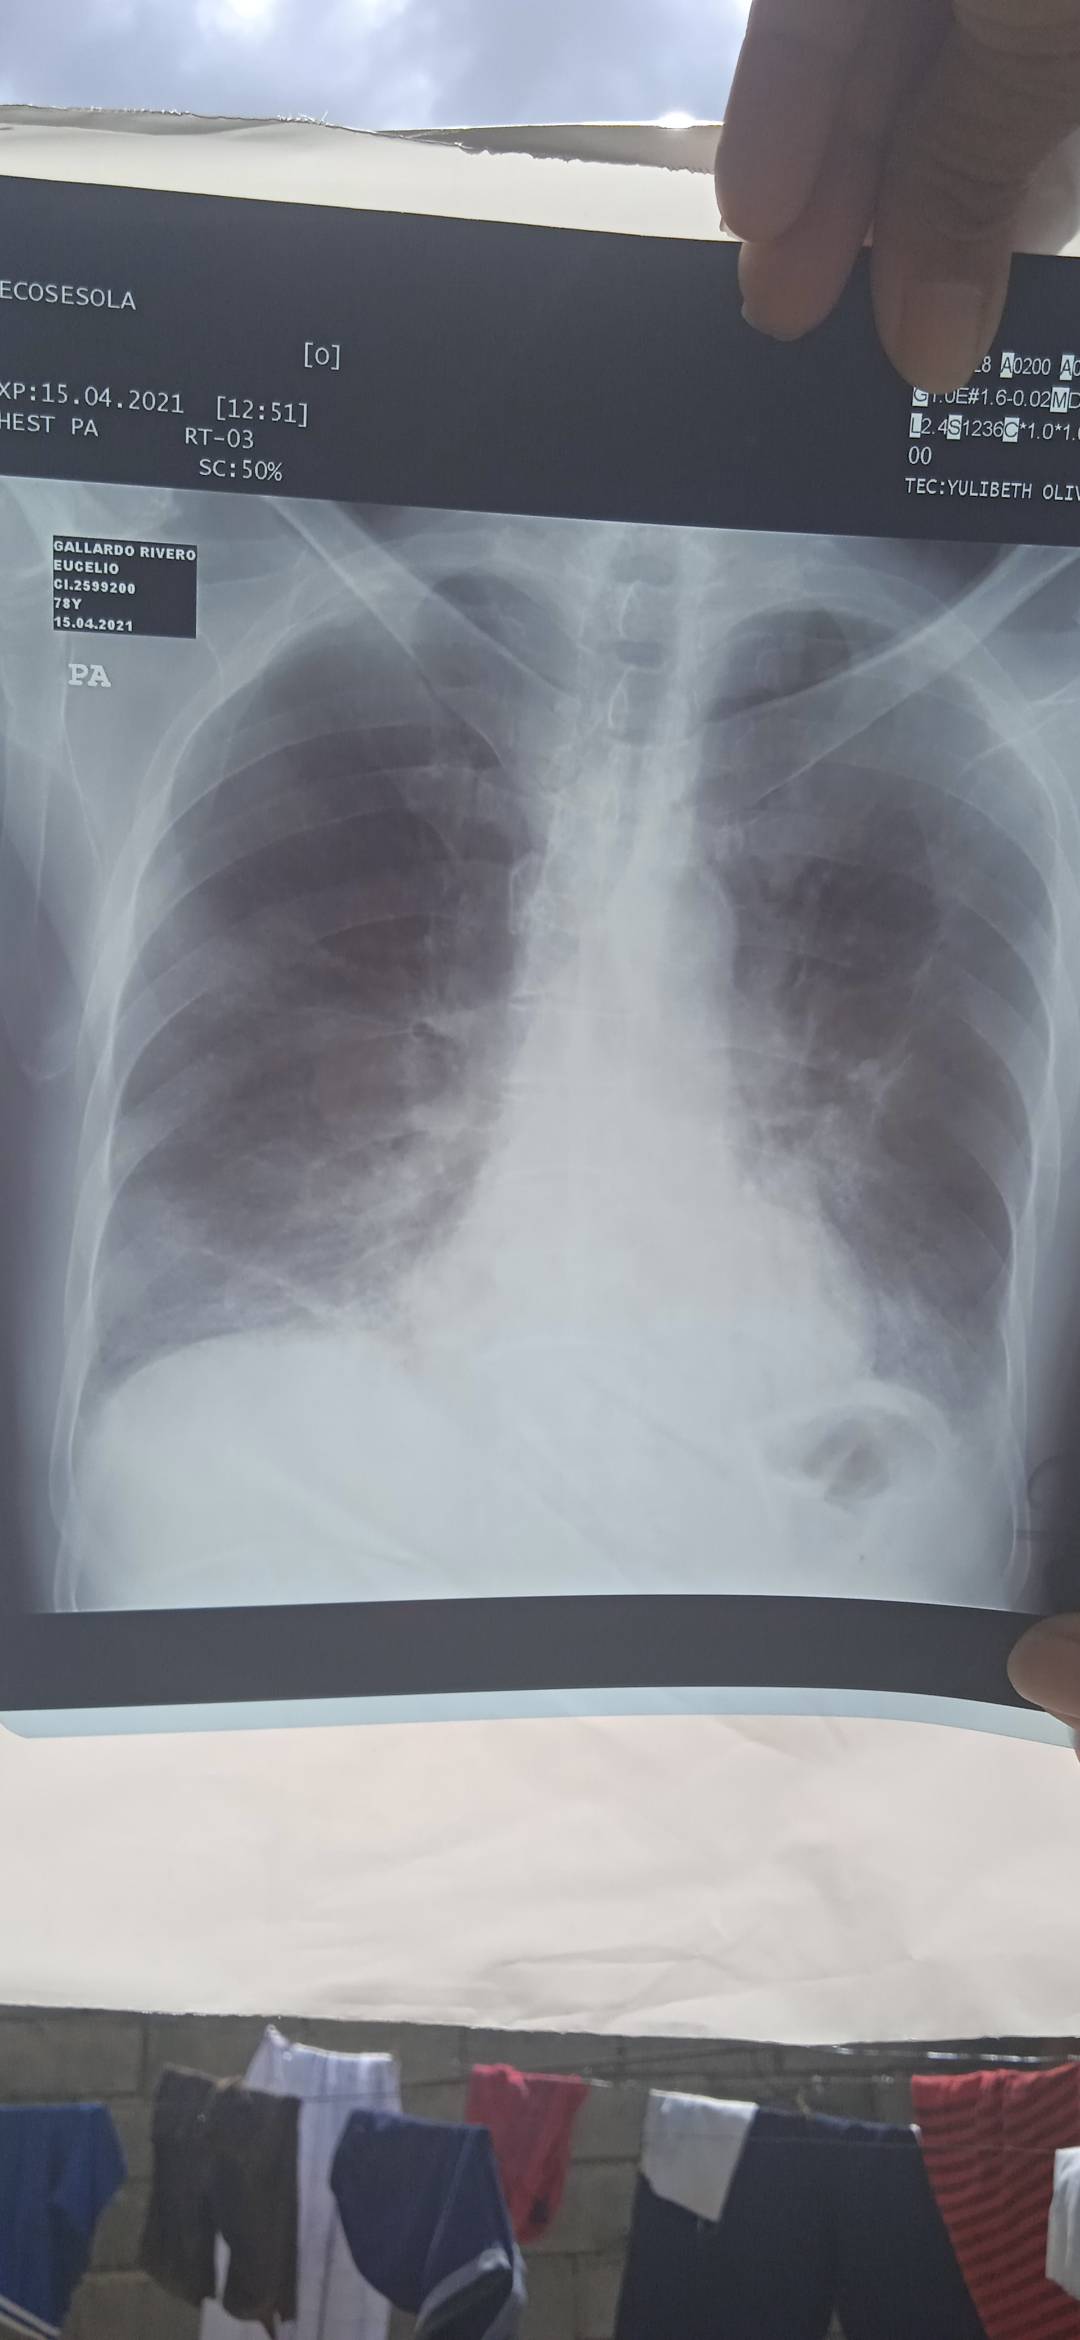

Hola soy enfermero y trabajo en un sentinela con pacientes covid, en venzuela, resulta Este extraordinario como mi gobierno hasta en armas y lujos, mientras mueren personas. A diario en estos centros carentes no tanto de lo básico sino de elementos y dispositivos como estás el dropeep. Este equipo no lo tenemos en nuestro centro y llevo meses buscando donativos para pode adquirirlo y proponer usarlo en nuestros pacientes. Esto permitiría aumentar la tasa de supervivencia. Espero su ayuda con sus votos y comentarios . Ya que son dispositivos costosos las partes necesarias para armarlas.